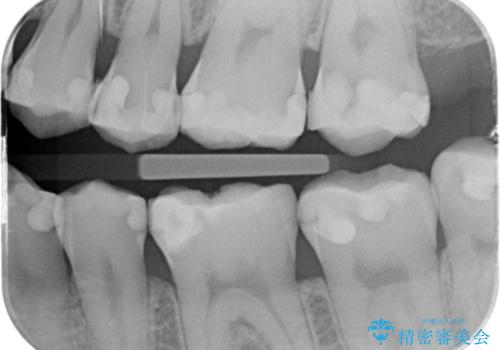

- 矯正前の患者様です。検査をしたところ虫歯が見られたので拡大鏡下で虫歯を取り除き

e-maxインレーで治療を行いました。

- e-maxインレー 7.7万×2費用は治療当時の料金となります